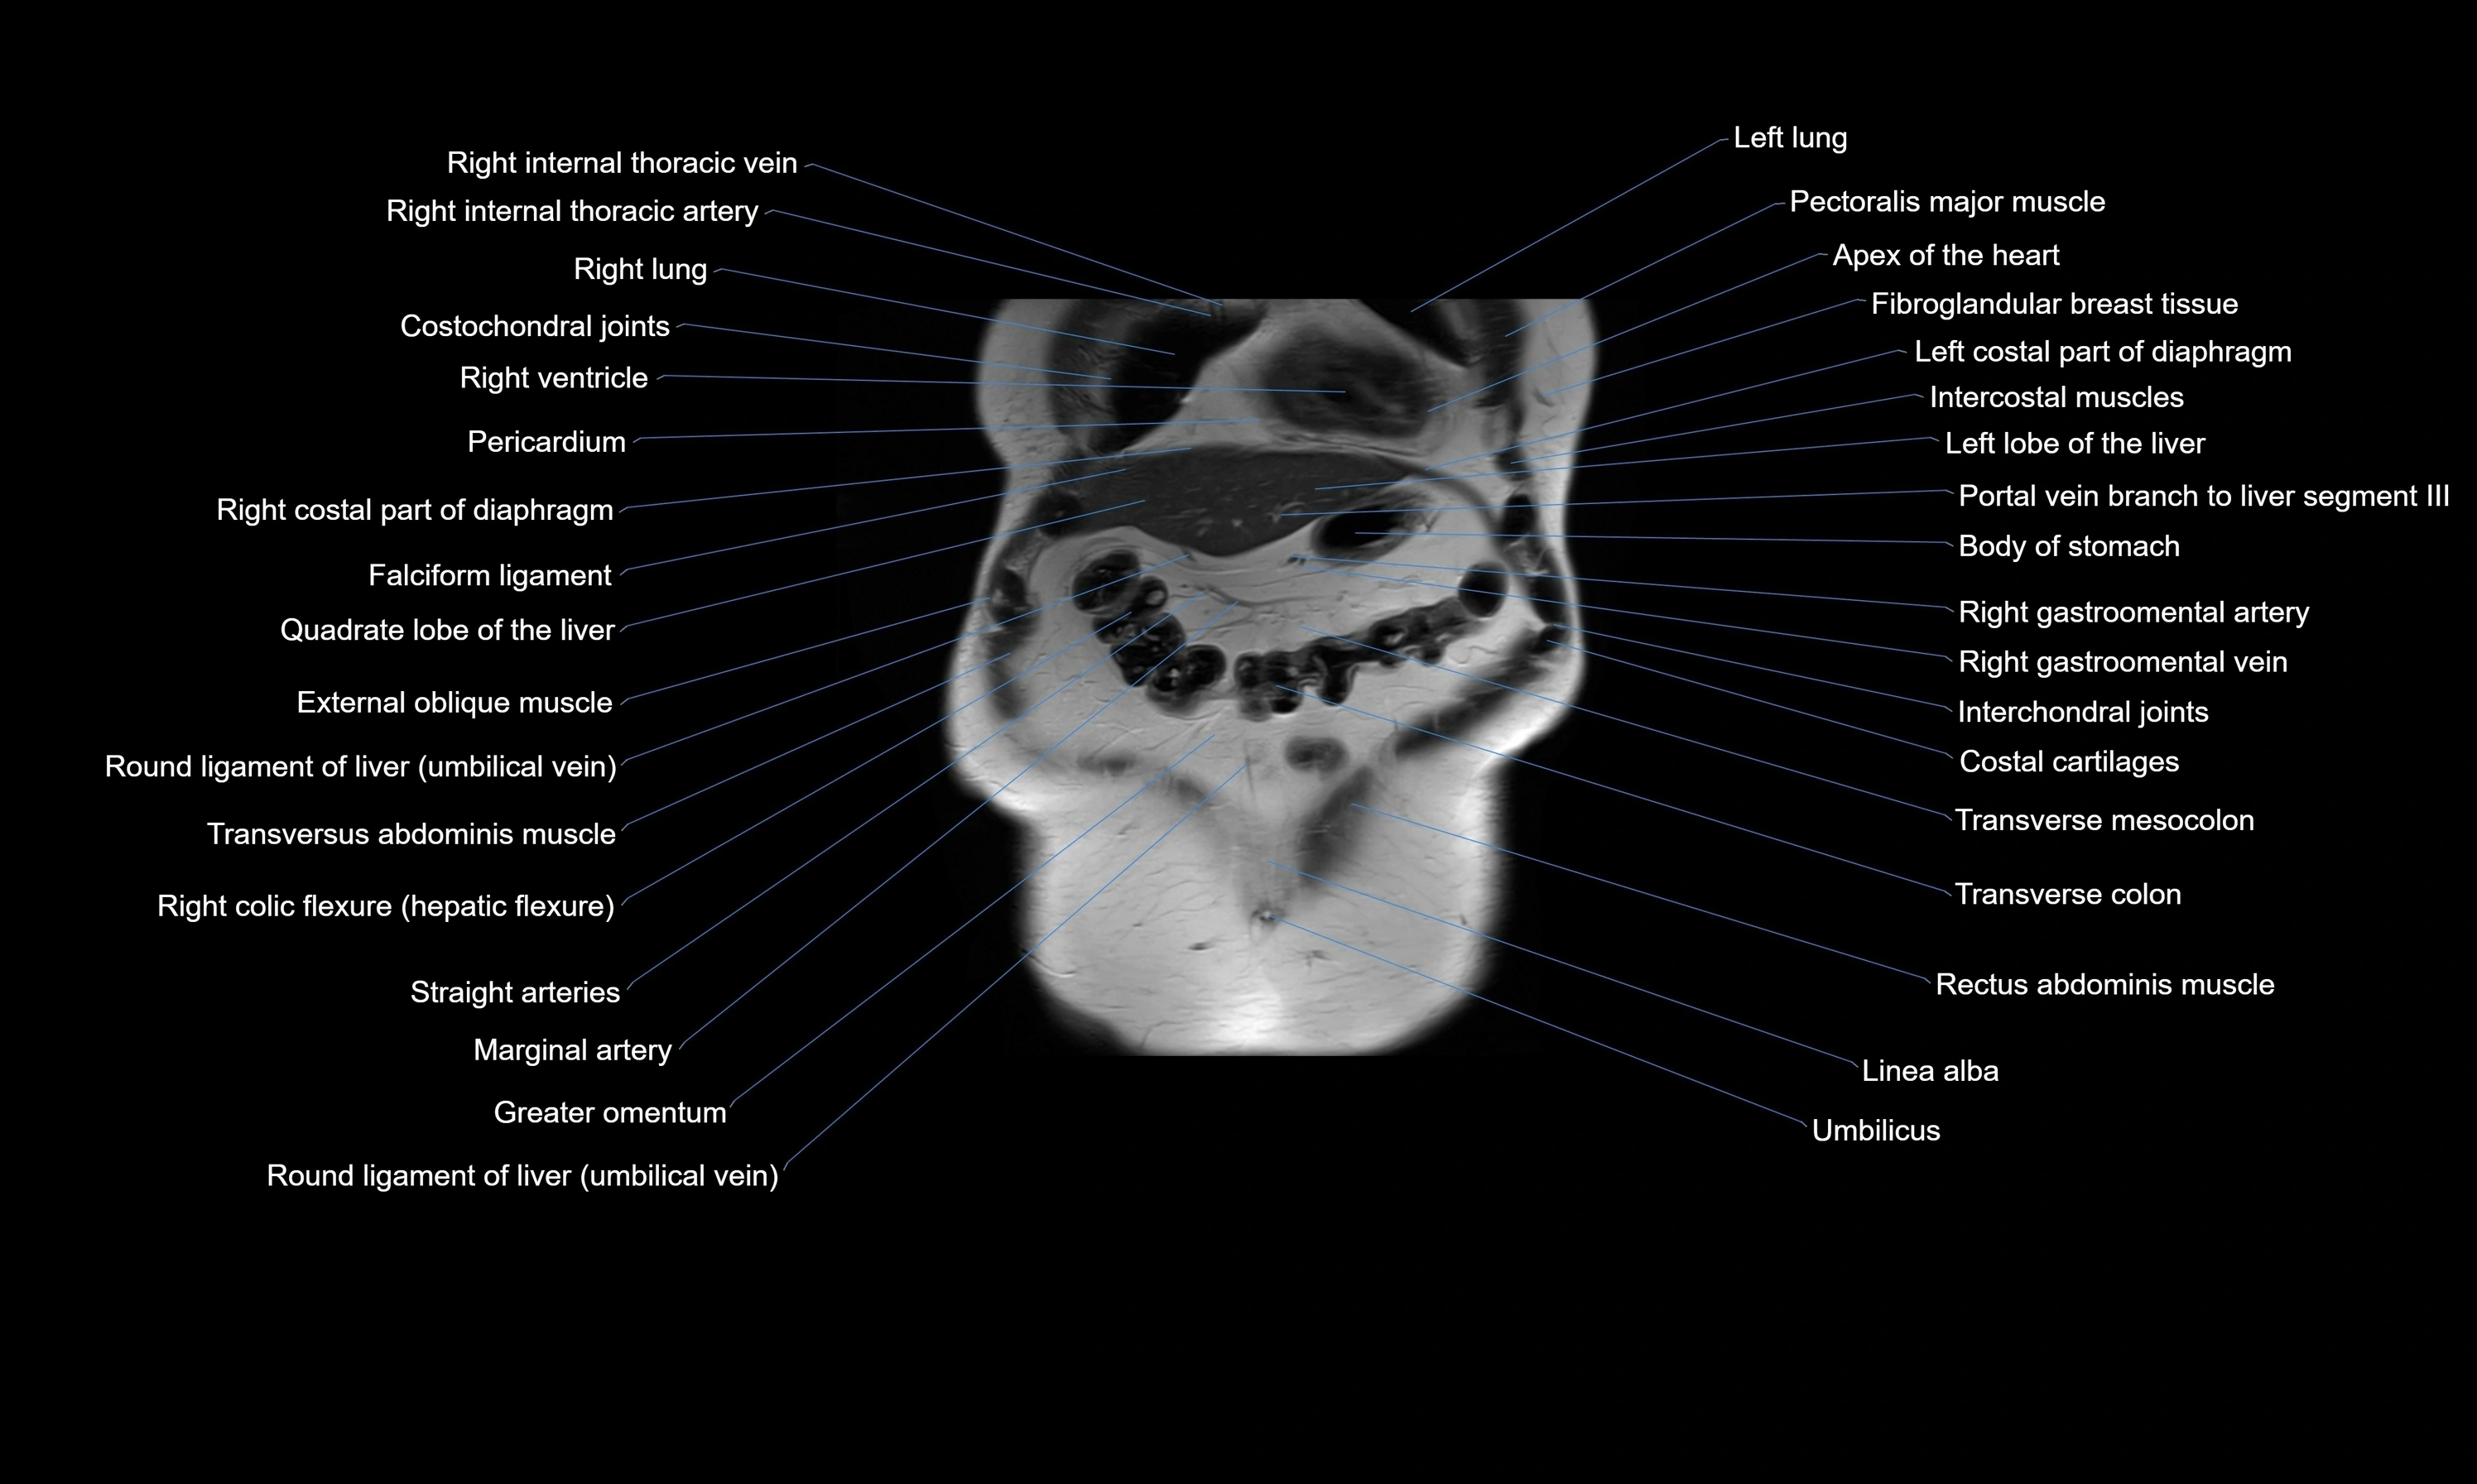

- Apex of the heart

- Costochondral joints

- External oblique muscle

- Falciform ligament (liver)

- Intercostal muscles

- Internal oblique muscle

- Linea alba

- Pericardium

- Quadrate lobe of liver

- Rectus abdominis muscle

- Right colic flexure (hepatic flexure)

- Right ventricle

- Transverse colon

- Transverse mesocolon

- Transversus abdominis muscle